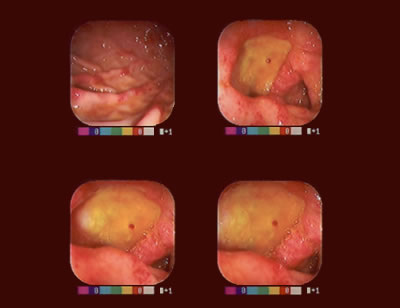

Serie Fotográfica: Estómago y Duodeno

Úlcera prepilórica con vaso visible.